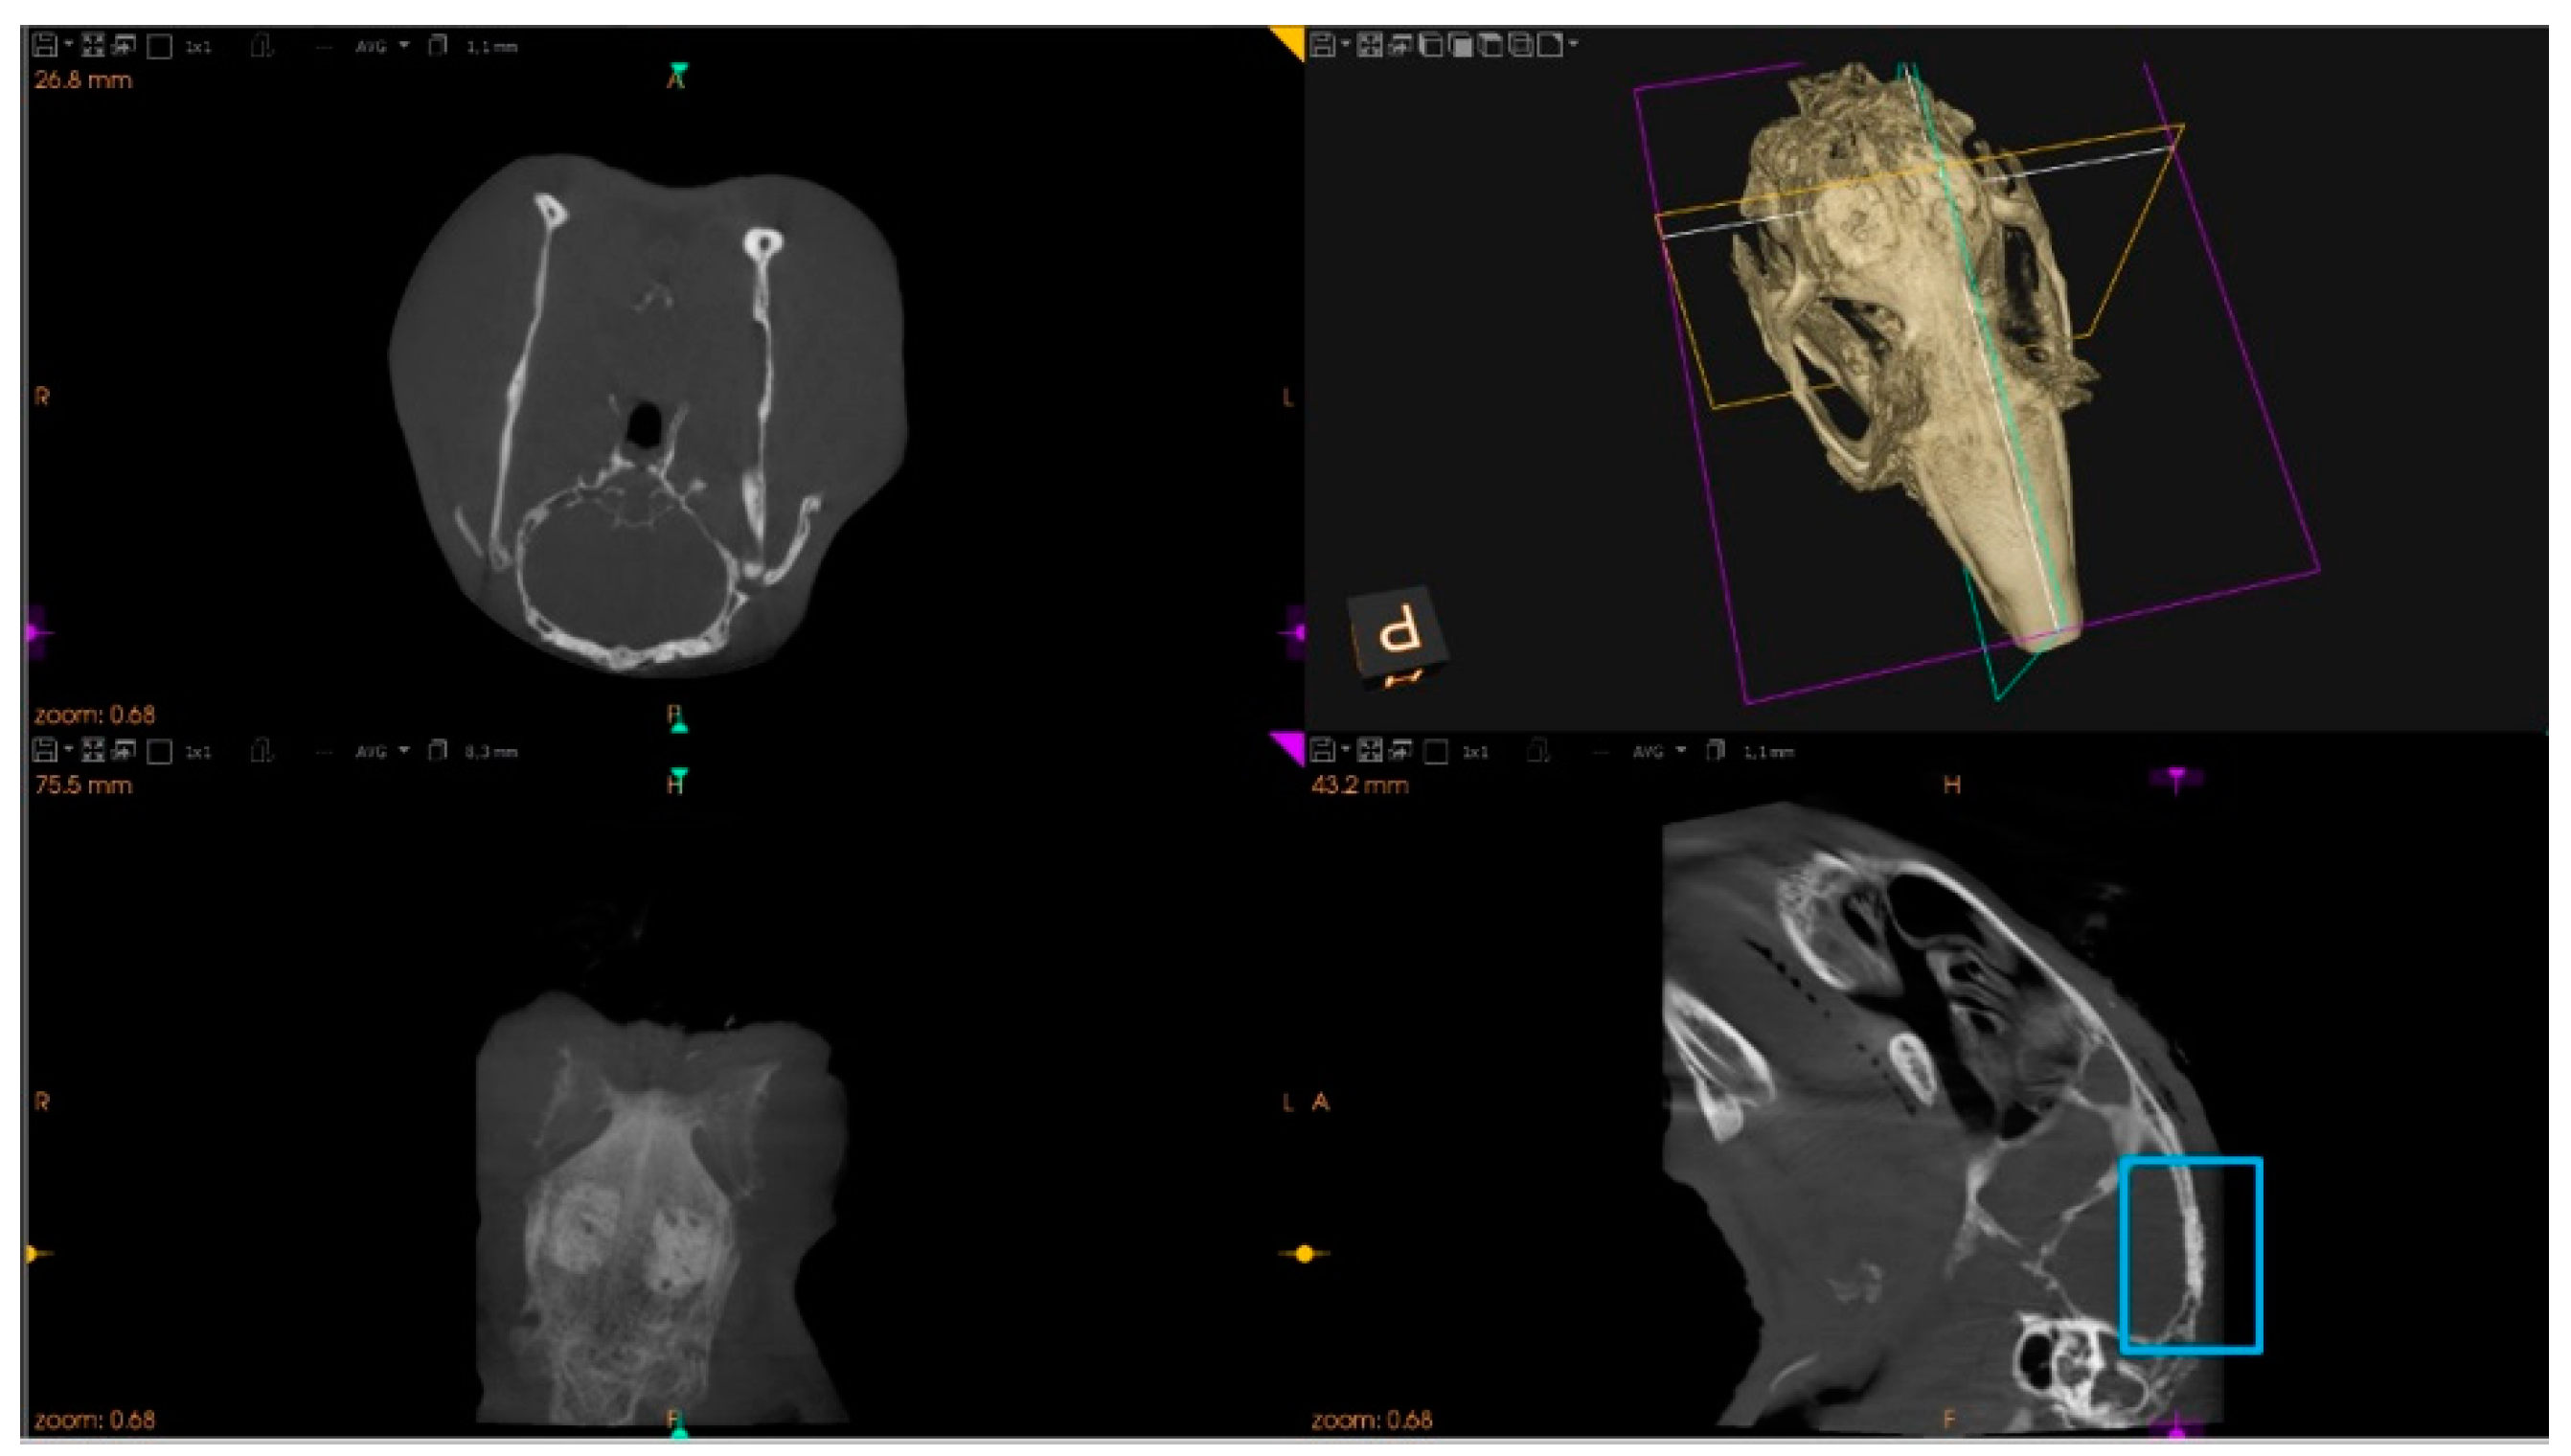

2.7.1. Microtomographic Evaluation